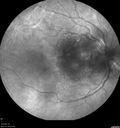

81 year old woman with vision loss in the right eye for a few weeks. She presented on oral antibiotic for preseptal cellulitis but had restricted eye movement from orbital cellulitis. Vision was LP right eye and 20/32 left eye. She went to the hospital and was admitted for IV antibiotics. She had no orbital abscess. Ultimately the right eye became NLP and she developed a necrotic retinal detachment and corneal neurotropic ulcer. The FA in this case shows brisk circulation. I presume she had a CRAO in the recent past and the central artery had reperfused. Left eye has Dry AMD.

Orbital Cellulitis - Optic nerve compression with ocular ischemia560 views81 year old woman with constricted eye movement, orbital cellulitis and severe vision loss in the right eye (LP). She has whitening of the retina and the OCT shows ischemic changes as well as subretinal fluid and blood. The vision in this eye declined to NLP and the eye remained ischemic despite control of her infection.     (0 votes)